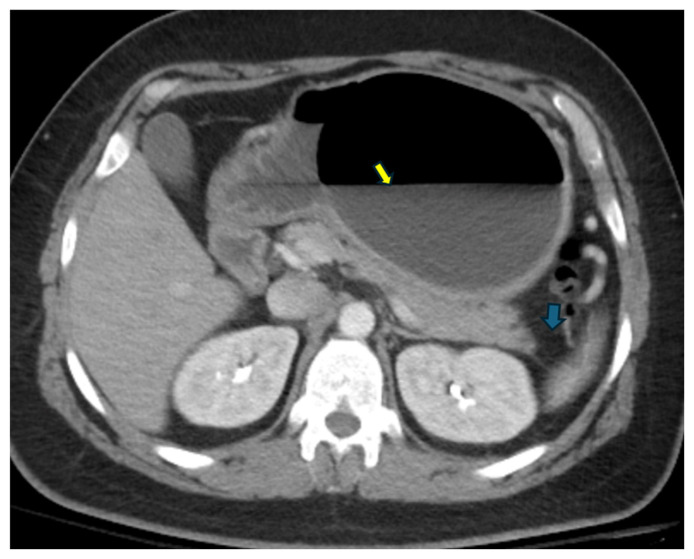

胃内球囊置入术(IGB)是一种治疗肥胖的微创干预手段,可导致一系列并发症,从轻微的胃肠道症状,如恶心、呕吐、腹痛和胃食管反流(GERD),到更严重和危及生命的疾病,包括穿孔、球囊迁移和胰腺炎。igb相关性胰腺炎是一种罕见的并发症,但在文献中有报道。本病例报告是一例罕见的由IGB引起的胰腺炎,并在球囊切除后得到完全解决。

Intragastric balloon (IGB) placement, a minimally invasive intervention for obesity, can lead to a range of complications from mild gastrointestinal symptoms such as nausea, vomiting, abdominal pain, and gastroesophageal reflux (GERD) to more severe and life-threatening conditions, including perforation, balloon migration, and pancreatitis. IGB-related pancreatitis is a rare complication, but it is being reported in the literature. This case report presents a rare cause of pancreatitis induced by IGB, with complete resolution achieved following balloon removal.